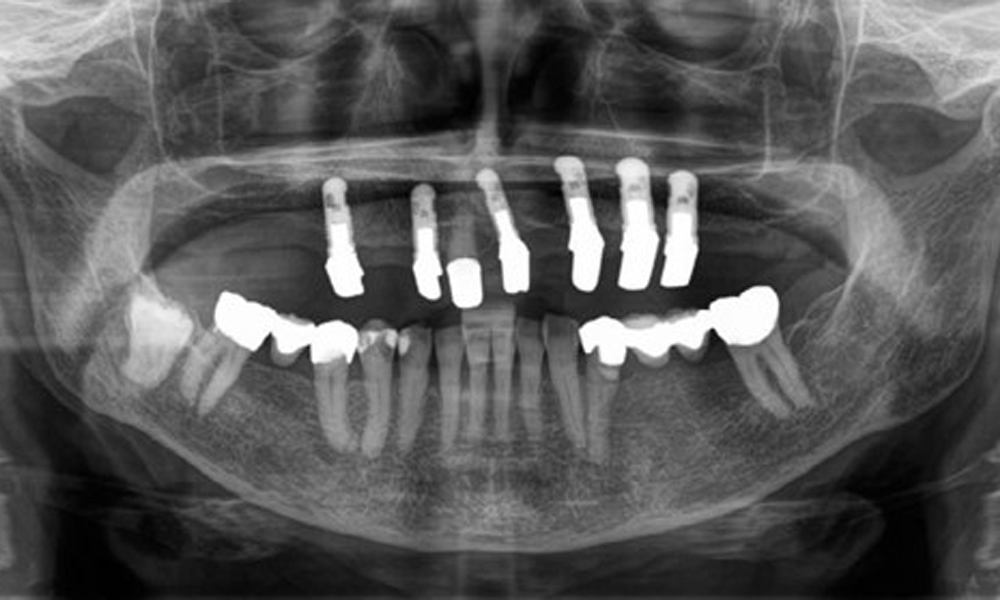

The patient was fitted with a combined removable maxillary telescopic prosthesis more than 25 years ago (Fig. 1, Fig. 2, Fig. 3) and is very happy with her dentures. The patient has an adequate fixed denture for the mandible (Fig. 4).

The dental findings are as follows: Combined removable implant and tooth-supported telescopic prostheses on implants 15, 13, 21, 23, 24, 25 and tooth 11 (Fig. 1, Fig. 2, Fig. 3). The patient was fitted with a fixed mandibular denture. Adequate bridges were present over 37 to 34 and 45 to 47 (Fig. 4), the crown margins were intact and there were no active caries. A composite filling with a marginal gap was present on tooth 43. There was mandibular gingival recession, exposing 1 to 3 mm of root surface. This also applies to 11.